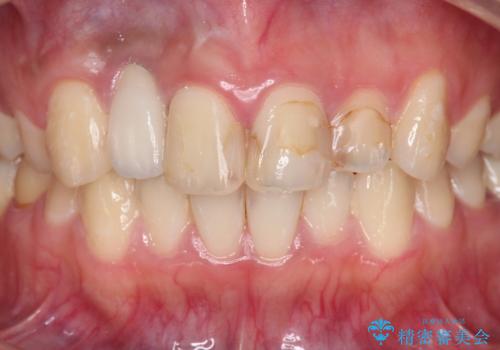

- 虫歯の治療を繰り返した前歯の見た目の改善を求めて来院されました。

大きく詰められたコンポジットレジンと虫歯の再発が見られ、経年劣化により審美性も損なわれていました。

充填されたコンポジットレジン・再発した虫歯を神経に影響が出ないよう丁寧に除去し再充填をしたのちオールセラミッククラウンで前歯の審美性を回復します。

※右上2のインプラント治療は他院のものです。